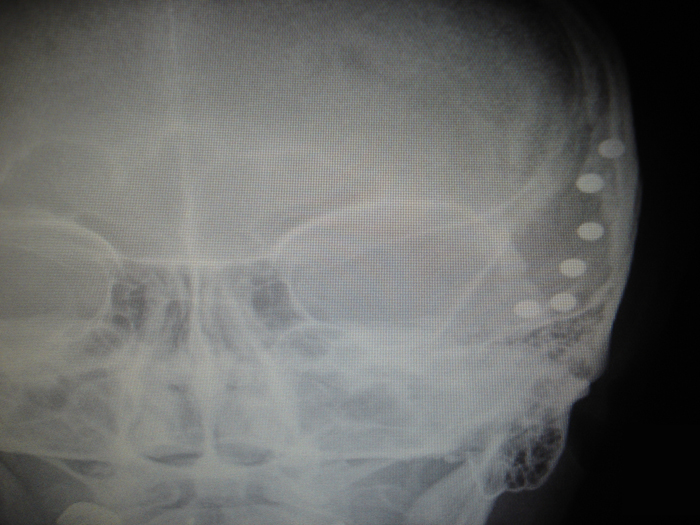

26.decembrī pulksten 6 neatliekamās medicīniskās palīdzības darbinieki slimnīcā nogādājuši 1958.gadā dzimušu vīrieti, kurš mēģinājis sev iešaut galvā ar pārveidotu gāzes ieroci, informē SIA "Ogres rajona slimnīca" valdes priekšsēdētājs Dainis Širovs.

Glābjot vīrieša dzīvību, veikta steidzama operācija.